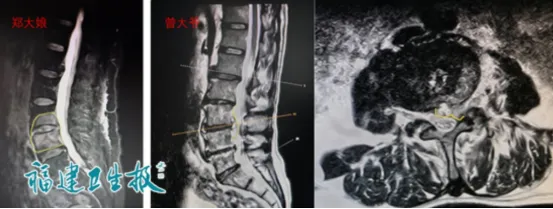

? ? 几天后,省疾控中心的检测结果传来——夫妻俩均为“布鲁氏菌抗体阳性”;核磁共振检查也显示,两人的腰椎椎间隙及相邻椎体都有明显炎症信号。

? ? 其中,曾大爷的情况更危急:腰椎不仅已经化脓,炎症还侵犯了椎管,腰椎变得极其不稳定,随时可能出现下肢麻痛、无力,甚至瘫痪、大小便失禁等严重后果。

术前影像